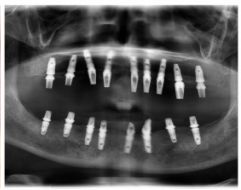

種牙后X光片,未戴冠。

通過X光片可以看到,醫(yī)生雖然盡量設(shè)計(jì)連冠種植,但還是用了十七個(gè)植體,盡管已經(jīng)是多次調(diào)整后的精簡(jiǎn)方案,但手術(shù)時(shí)長(zhǎng)依然長(zhǎng)達(dá)一天。位老先生之前在另一家醫(yī)院咨詢時(shí),醫(yī)生給的方案是種二十二個(gè)植體,光是種植費(fèi)用就令人大呼“害怕”了。